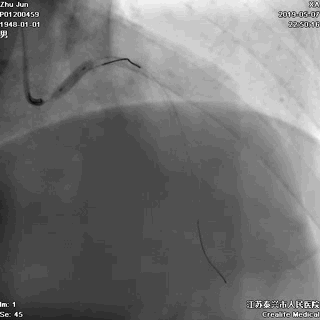

二、导丝到位

---筑牢生命线

导丝分别进回旋支和前降支

LAD和LCX,任一根血管都不能丢!这一步的价值,就相当于是构筑生命线。